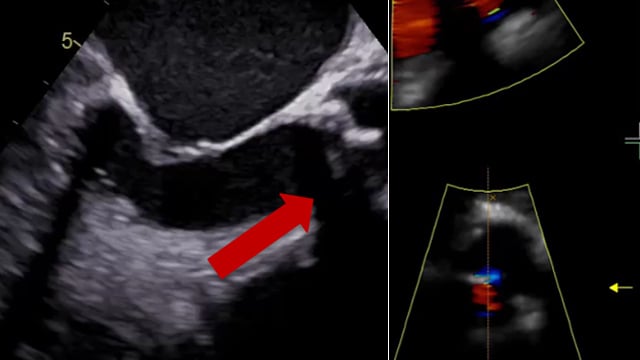

Nightmare in TAVI

08 Feb 2025 – From PCR Tokyo Valves 2025

Watch this session replay featuring two challenging cases: valve embolisation with a balloon-expandable valve and coronary obstruction with a self-expandable valve. Learn key lessons from the first case, including the importance of secure pacing, avoiding damage to the descending aorta while retrieving the embolised valve, and...